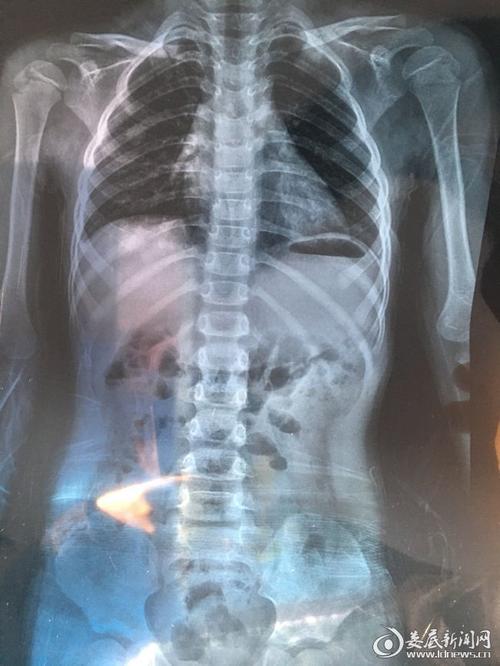

病例:7岁女生经4个月7d治疗,脊柱回直!